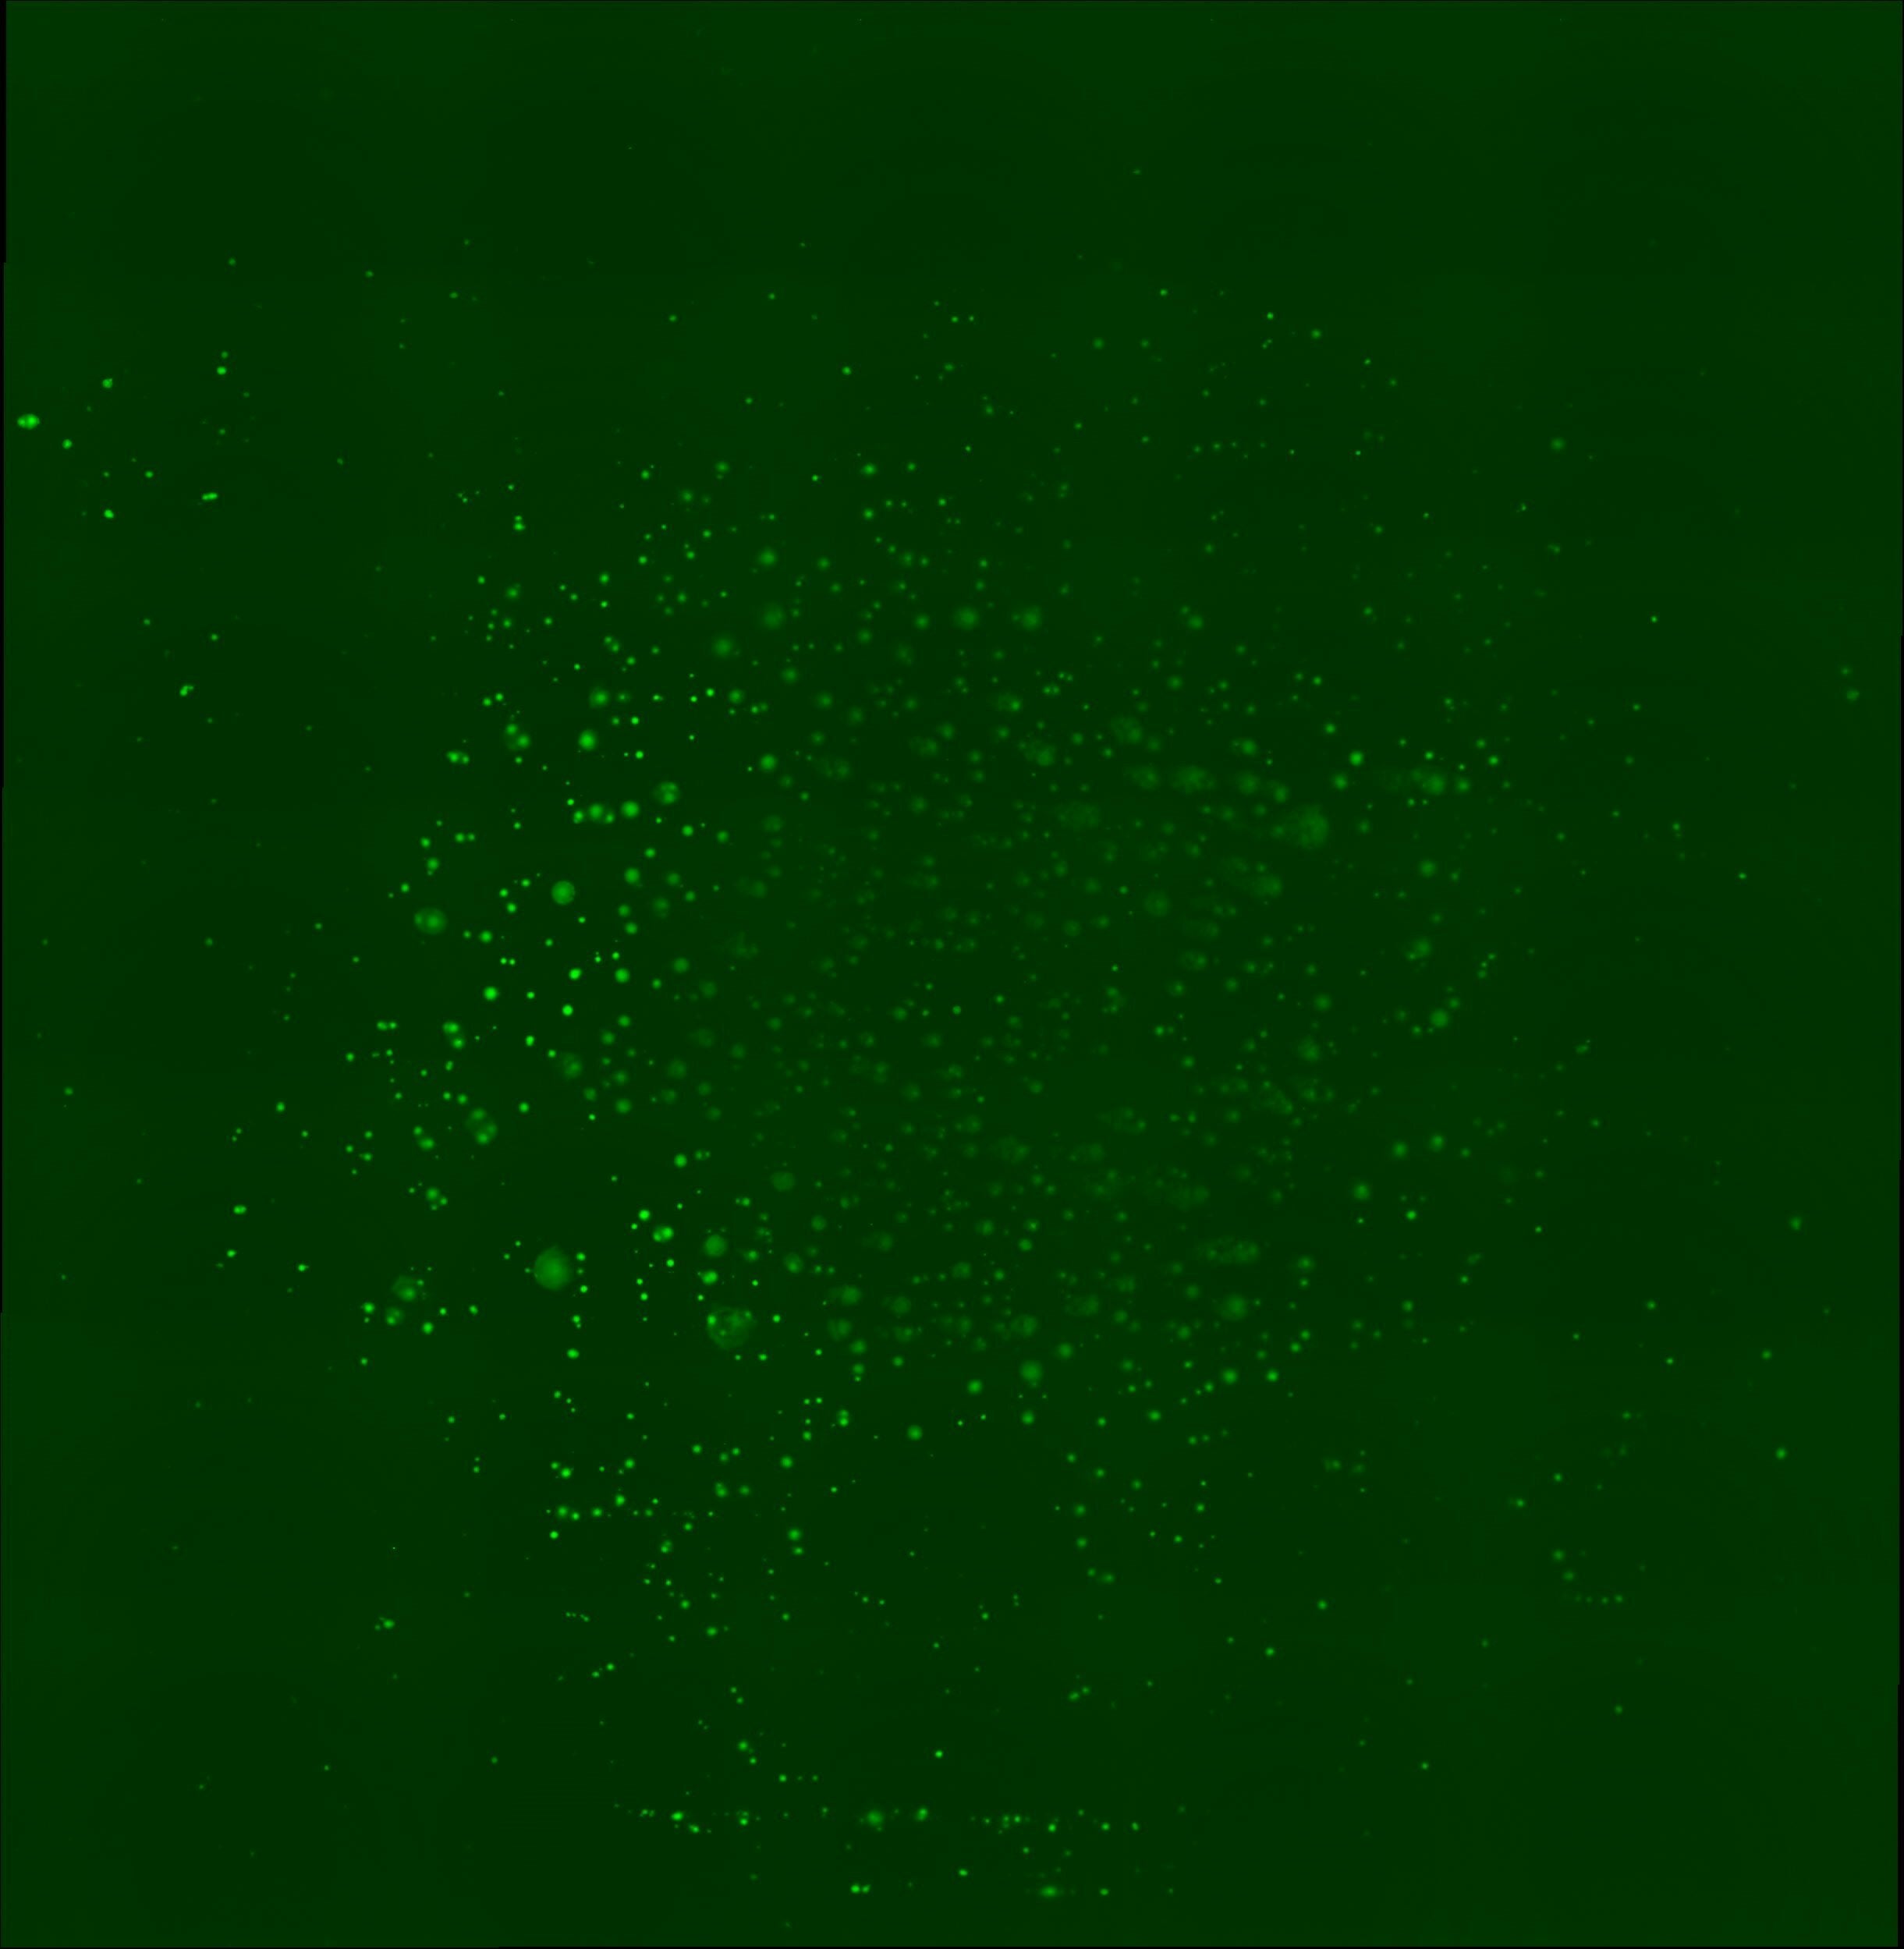

国内外の医療機関・メディアが注目する新たながん検出方法、昼夜問わず没頭し親子で挑んだ「プロテオ®バイオチップ」の開発秘話